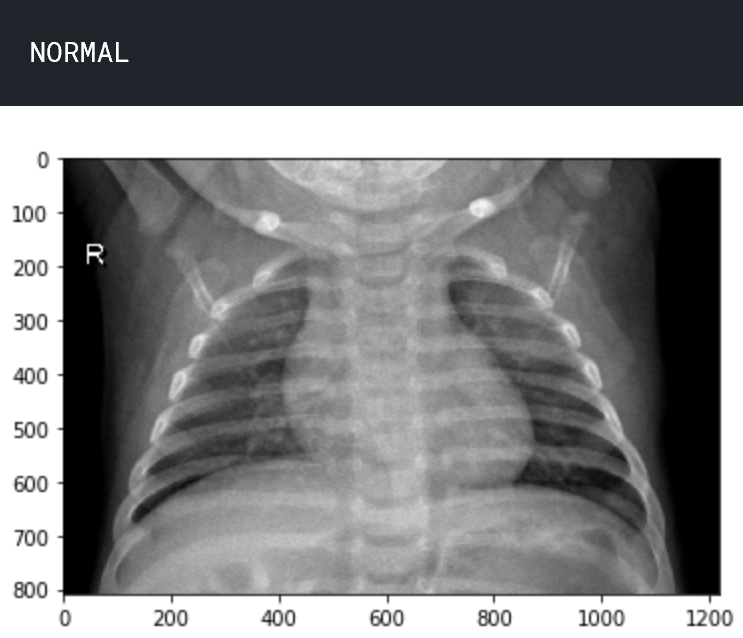

让我们了解数据。查看两个样本图像,一个处于正常状态,另一个处于肺炎状态。

img_name = 'NORMAL2-IM-0588-0001.jpeg'

img_normal = load_img('../input/chest_xray/chest_xray/train/NORMAL/' + img_name)

plt.imshow(img_normal)

plt.show()